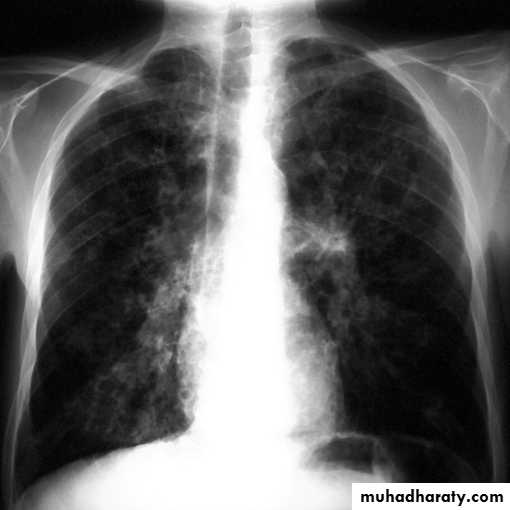

Alveolar shadow (consolidation )

Replacement of air in the alveoli by fluidContain (air bronchogram )

Pneumonia

Pulmunary edemaContusion